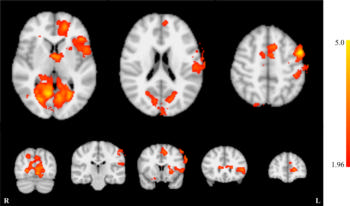

Figure 5. Whole brain effects of neurofeedback training.

High-res (TIF) version

Figure 7. Activation of the primary auditory cortex in response to binaural stimulation. Activation significantly decreased from session 1 to session 5.